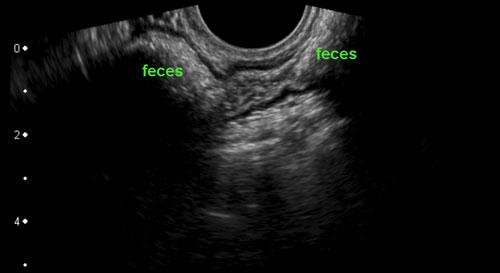

Hình ảnh giải phẫu TVUS của đại tràng sigma bình thường, có khả năng đè xẹp tốt, được khảo sát trên mặt cắt dọc và mặt cắt ngang.

Ở cuối chuỗi hình, trên mặt cắt ngang, đại tràng sigma dễ dàng bị đè xẹp bởi đầu dò (đầu mũi tên) áp vào xương cùng.